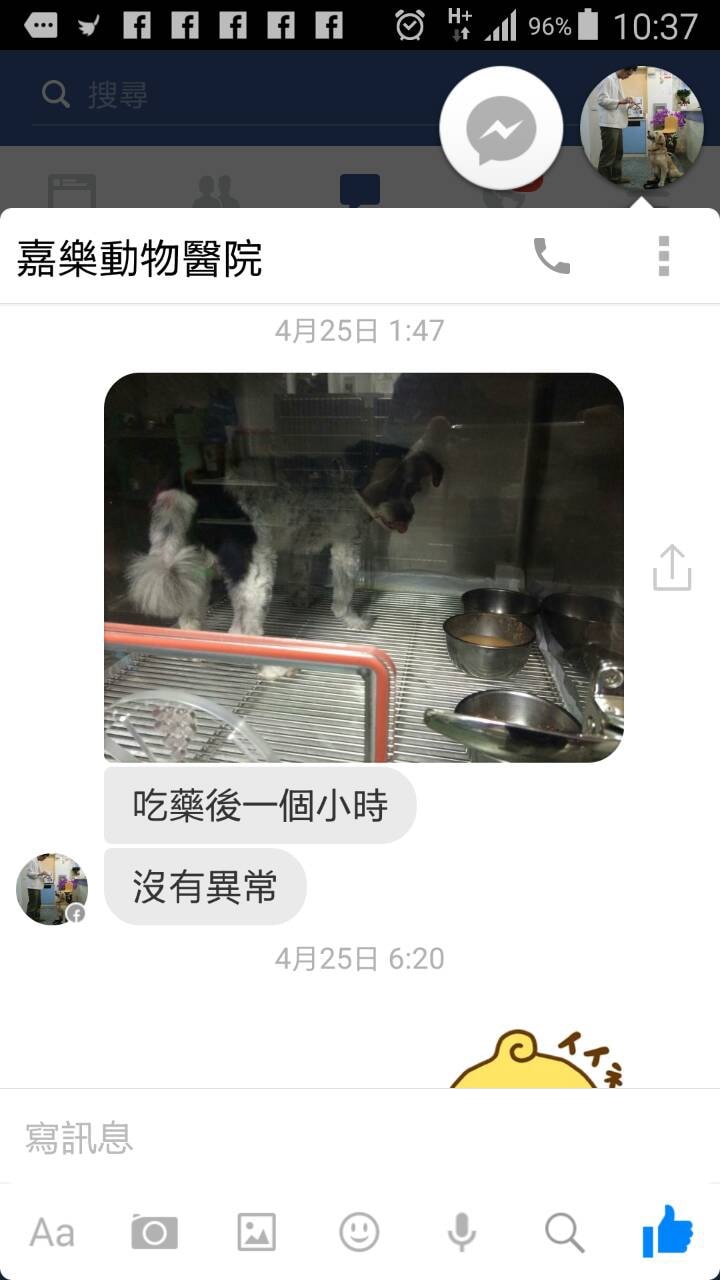

點點就診的動物醫院真的非常貼心,還即時傳訊息跟Sunny說明病況

看到醫院傳來點點住進氧氣室的照片,Sunny當下就哭了 TAT

嘉樂動物醫院的醫師和助理就醫服務真的很好

期間一直陸續主動告知點點的病況,比如:剛打過針了、能趴下睡覺了、喘的情形….等

讓主人可以即時得到安慰,雖然Sunny每看一次簡訊就哭一次….(淚水停不住)

打開手機,發現凌晨一點多,動物醫院還有發訊息告知觀察點點吃藥後的狀況

真的覺得醫生(助理們)好辛苦!!!這麼晚在注意點點的病況

也謝謝他們這麼用心的照顧點點

中間嘉樂動物醫院持續有傳來點點狀況

讓Sunny雖然身在”會議”,心在”點點”,也都能即時同步到點點的病況(感到安慰)